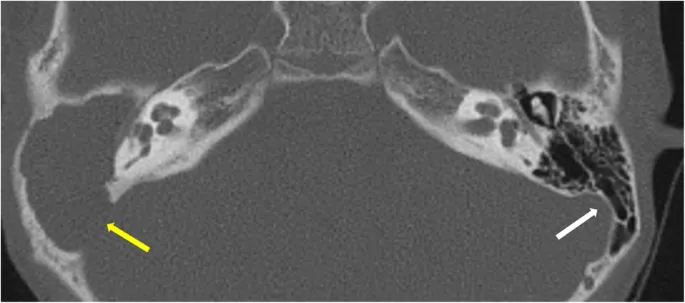

- HRCT Temporal Bone: Assesses cholesteatoma extent, bony erosion, ossicular chain integrity.

ā High-Resolution Computed Tomography (HRCT) of the temporal bone is the imaging modality of choice to assess the extent of cholesteatoma and bony erosion.